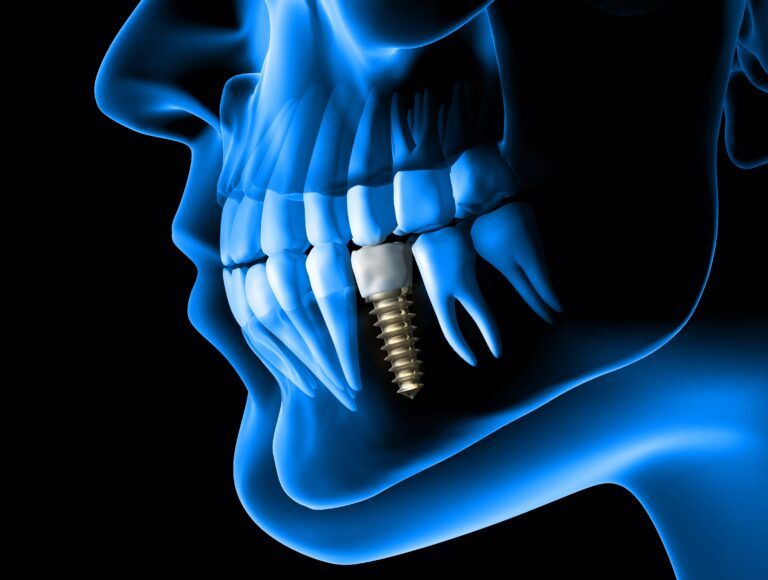

The Step-by-Step Process of Dental Implant Placement

Dental implants represent a groundbreaking advancement in restorative dentistry, offering a durable solution for replacing missing teeth and enhancing oral functionality. These artificial tooth roots, typically made from titanium, are surgically inserted into the jawbone, providing a strong foundation for

Step-by-Step Guide to the Dental Implant Process

Dental implants have become a revolutionary solution for restoring missing teeth, offering both functionality and aesthetics. Patients at New Teeth Chicago Dental Implants in Chicago, IL, often seek guidance on what to expect during the implant process. Dr. Irfan Atcha